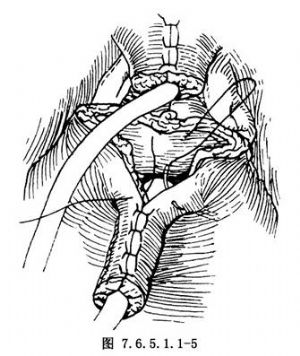

5.將瓣的基部與膀胱三角區的尖部縫合,然後橫行縫合兩側剩餘的膀胱壁(圖7.6.5.1.1-5)。